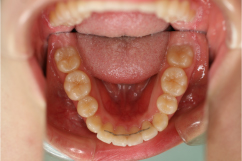

叢生(そうせい)

治療前

治療後

| 主訴 | 著しい乱ぐい歯、口元の突出 |

|---|---|

| 診断名 | 著しい叢生のClass l不正咬合 |

| 初診時年齢 | 21歳1か月 |

| 主な治療装置 | マルチブラケット装置、歯列弓拡大装置 |

| 抜歯部位 | 上下顎左右第一小臼歯の抜歯 |

| 治療期間 | 2年1か月 |

| 治療費 | 矯正治療基本料:60万円 / 調整料 3,000~5,000円×35回 |

| リスク・副作用 | 矯正中は、口腔を清潔に保たないと、虫歯、歯肉炎、歯周病になるリスクがあります。マルチブラケット装置の使用には、口腔内の刷掃や治療協力が必要です。成人では、強い歯ブラシ圧によって歯肉退縮が起こることがあるので注意して下さい。治療後の保定を怠ると、このような症例では、後戻りが容易に起こるので長期管理が必要です。 |